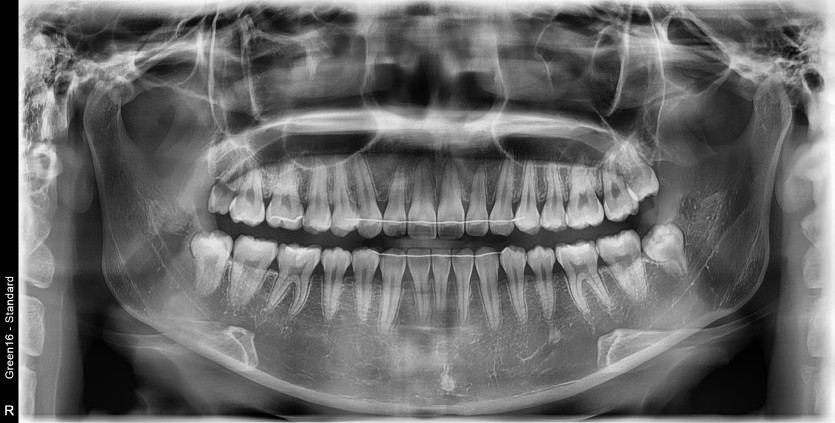

#18,28,38,48 사랑니 발치

구강 외과 전문의가 당일 발치했습니다.